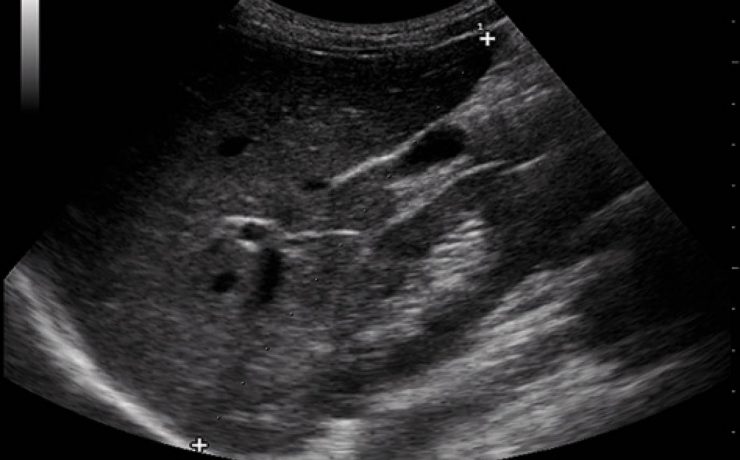

Escrito por Irene Arnanz González en 2014, hace la descripción de una paciente de 94 años quien ingresó a la consulta médica por prurito e ictericia con examen físico sospechoso por lo que se indicó ultrasonido de vías biliares con resultado de vesícula con pared gruesa de hasta 1cm de